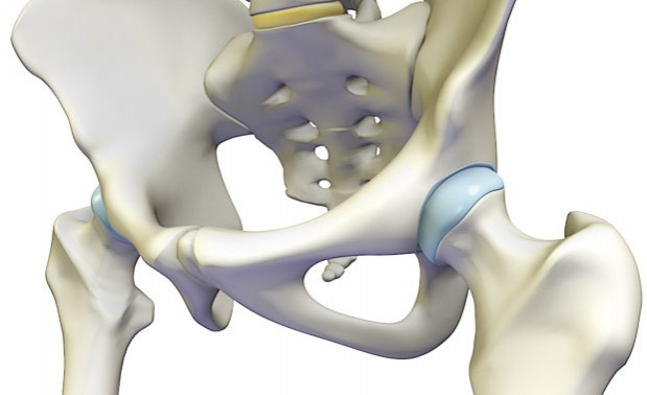

- Kolk

Kolki: nasveti in vaje za odpravljanje bolečin

Včasih so težave s kolki zelo očitne - bolečine so...

Poškodovan labrum kolka – kako ukrepati?

Do poškodbe labruma kolka običajno pride zaradi več razlogov. Glavni...Izpostavljeno